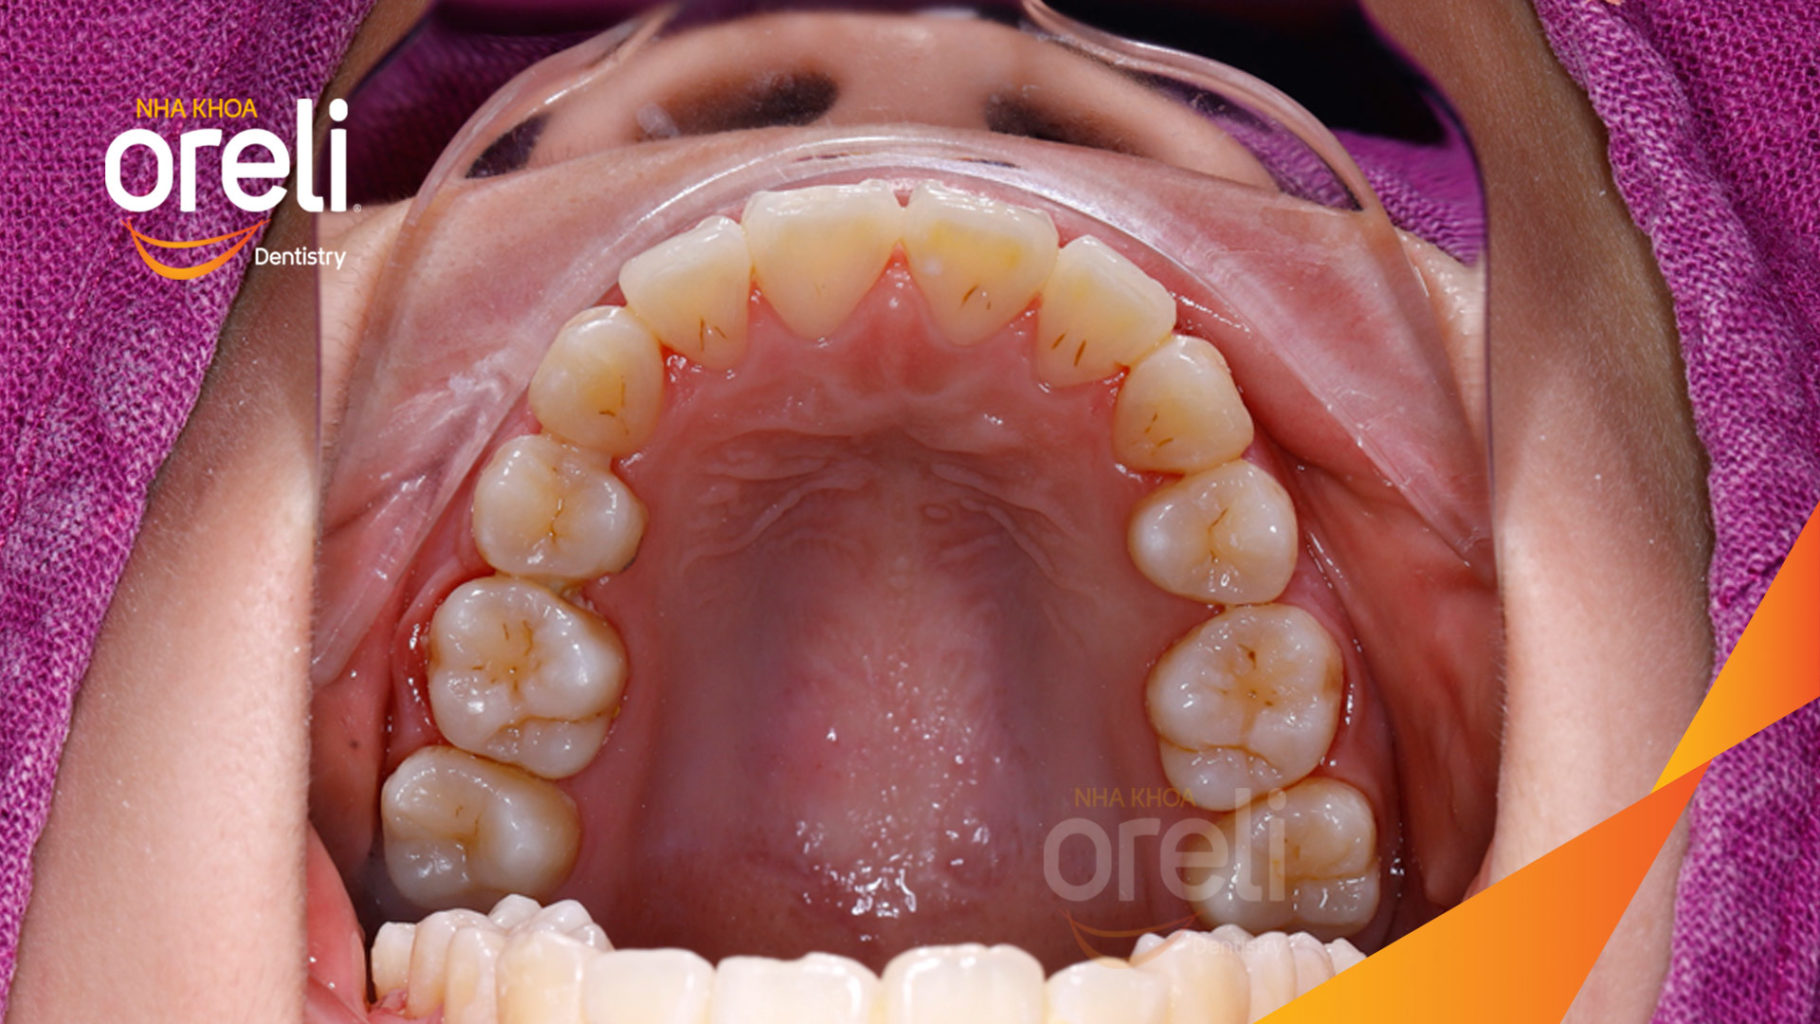

Ca niềng chỉnh chen chúc hẹp hàm nặng cả trên và dưới – Kết quả điều trị thực tế tại nha khoa Oreli

Ca niềng răng chen chúc phục hồi ăn nhai và thẩm mỹ nụ cười. Kết quả thực tế trước và sau điều trị tại Nha khoa Oreli.

Hình ảnh thực tế